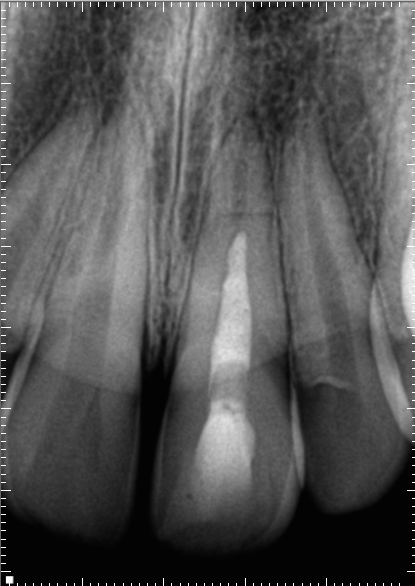

#4 RCT(2025.1.29)

術後にPA, CBCTを撮影した。

ここから1年が経過した。

#4 RCT 1yr recall(2025.12.24)

臨床症状, 術前の歯根膜腔隙の拡大はともに消失した。

ということで、#4の経過観察も終了でいいだろう。